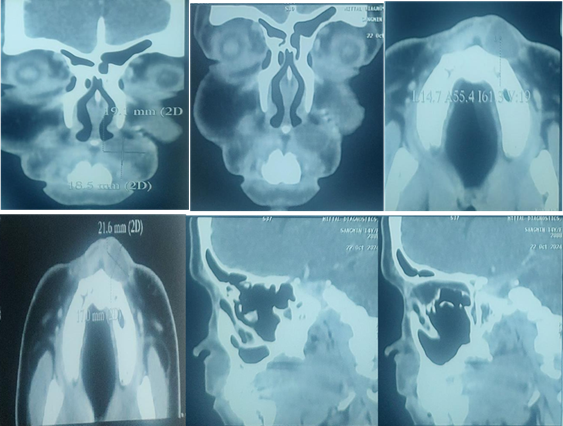

Non-contrast CT of the face was done and it revealed one well-defined hyper-dense lesion on the left side of the nasal ala at the nasolabial fold. The lesion measured (22x 19) mm in largest diameter. There was no evidence of bone erosion (Figure 2).

Figure 2 NCCT face (coronal, axial and sagittal cuts) showing a cyst measuring (22 x 19) mm in largest diameter.